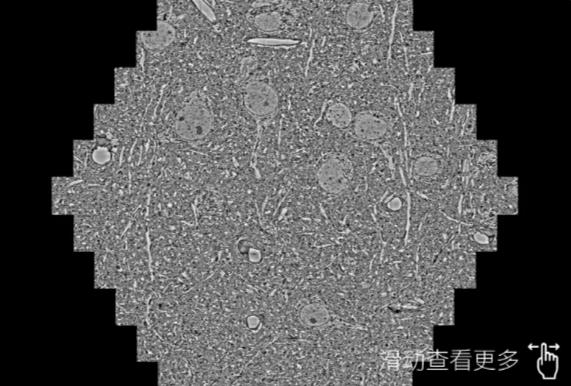

鼠脑切片。左图使用江西蔡司江西扫描电镜MultiSEM706对165μmx143pm面积区域成像,耗时仅需1.5秒。右图为鼠脑切片中30μm区域放大效果。样品由芝加哥大学B.Kasthuri提供。

使用蔡司高速江西扫描电镜MultiSEM对1mm²人脑皮层组织进行高分辨成像,并对其中的各种细胞结构进行三维重构分析。左图展示了2x3mm²组织平面中锥体神经元的三维重构效果。右图显示了局部体积神经元三维重构。图像由哈佛大学chtman实验室提供,渲染图由D. Berger 制作。